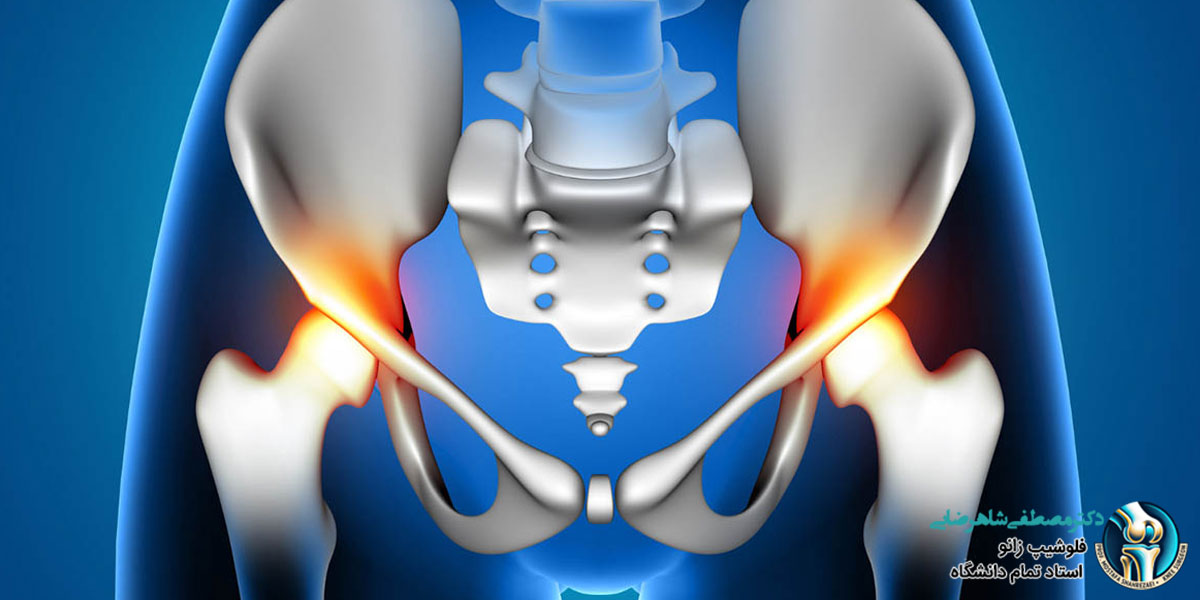

درد لگن یکی از مشکلات شایعی است که می تواند در هر سنی برای افراد پیش بیاید و انجام کارهای روزانه را سخت کند. این درد ممکن است به دلایل مختلفی مثل آسیب های عضلانی، مشکلات مفصلی یا بیماری های استخوانی ایجاد شود. گاهی اوقات این درد به خودی خود برطرف می شود، اما در مواردی ممکن است نشان دهنده یک مشکل جدی تر باشد که نیاز به درمان دارد. شناخت علل مختلف درد لگن و آشنایی با روش های درمانی مناسب می تواند به شما کمک کند تا راحت تر به دنبال درمان و بهبودی باشید.

درد لگن به دلایل مختلفی پیش می آید که در ادامه، رایج ترین علل ایجاد درد لگن را بررسی می کنیم:

- آرتروز (ساییدگی مفصل لگن): یکی از علت های شایع درد لگن، آرتروز است. این بیماری در اثر ساییدگی و فرسودگی مفصل لگن به وجود می آید و باعث درد، خشکی و کاهش حرکت می شود. این مشکل معمولا در افراد مسن دیده می شود.

- التهاب کیسه های مفصلی (بورسیت): در اطراف مفصل لگن، کیسه های کوچکی وجود دارند که از مفصل محافظت می کنند. اگر این کیسه ها ملتهب شوند، درد و ناراحتی در لگن به وجود می آید.